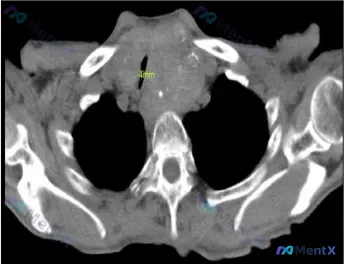

看到一份术前的颈部CT病例资料,影像特征非常有挑战性,尤其是气道压迫的程度很高,整理了一下完整的信息和分析思路,和大家分享讨论。 --- 病例核心影像与事实 - 甲状腺大小:左侧约 79 x 65 mm,右侧约 64 x 41 mm; - 气道评估:气管明显向右移位,最窄处直径仅 4 mm; - 软...